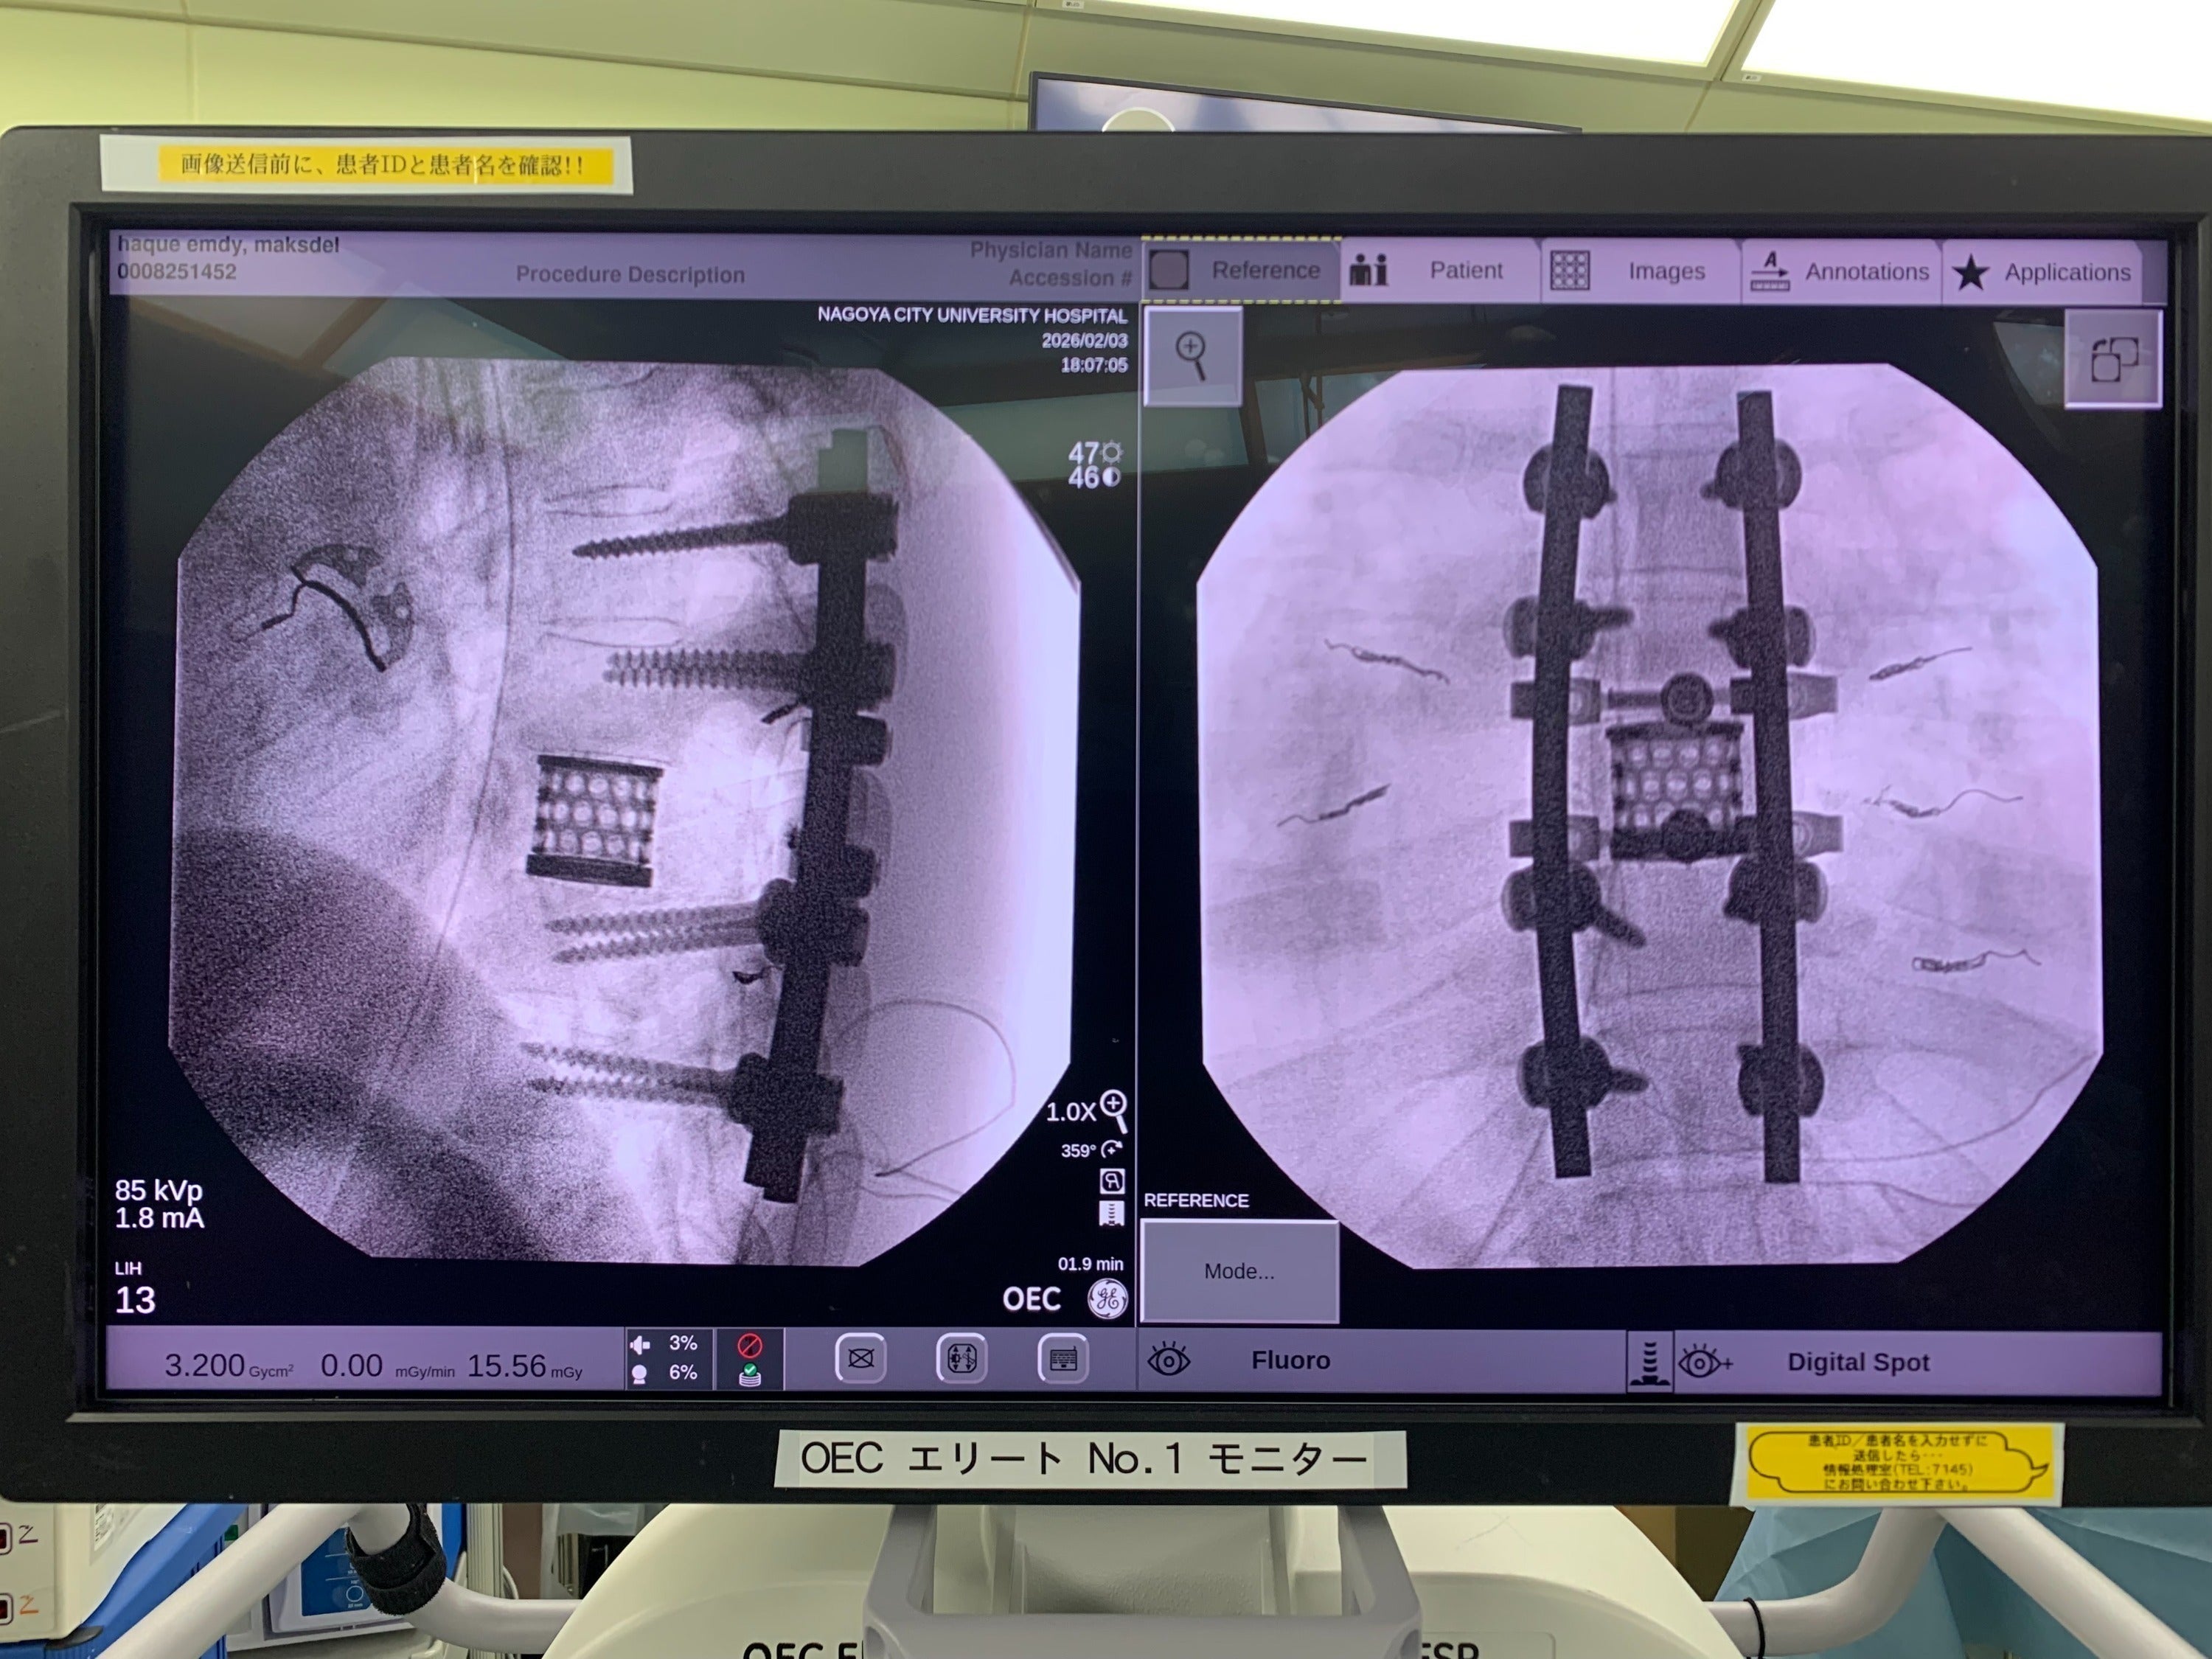

そして2025年2月3日。

ハクさんは 7時間を超える大きな手術 を受けました。

脊椎の腫瘍を取り除く手術はとても難しく、日本でも限られた医師しか行うことができない高度な手術です。

母国バングラデシュでは、この治療を受けることはできません。

定期健診に行きました

2026/04/16 20:57Last Friday, I had a routine checkup with Professor Murakami at Nagoya City University Hospital. He reviewed my X-ray and said that my condition is now good and will continue to improve day by day. However, the pain will persist, so I will need to take painkillers. Rehabilitation exercises should be done daily to speed up recovery.先週の金曜日に、名古屋市立大学病院で村上先生の定期診察を受けました。レントゲンを見ていただき、状態は良くなっていて、これからも少しずつ回復していくと言っていただきました。ただ、痛みはまだ続くので、しばらくは痛み止めを使いながら過ごす必要があります。また、回復を早めるために、リハビリは毎日続けるように言われました。 もっと見るハクです。近況をお伝えします